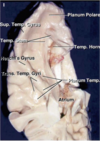

Key gyri on the lateral surface of the frontal lobe

Superior frontal gyrus

Middle frontal gyrus

Inferior frontal gyrus (pars triangularis, pars orbitalis, pars opercularis)

Precentral gyrus

Key sulci on lateral surface of frontal lobe

Superior frontal sulcus

Inferior frontal sulcus

Pre-central sulcus